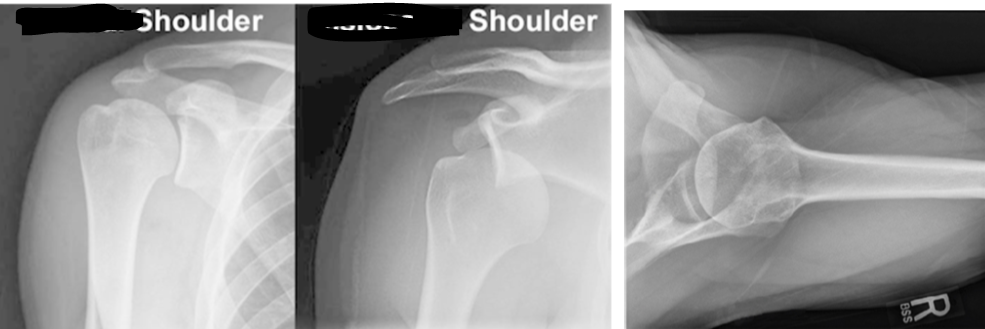

Shoulder Dislocation Imaging

Where is the ball in relation to the socket?

A

Ball in front of socket

• ______ view is mandatory in order to rule out a ______ dislocation

• Always need to study x-rays to rule out an associated proximal _______ fracture. (stat __ if unsure _______ reduction)

• Axillary view is mandatory in order to rule out a posterior dislocation

• Always need to study x-rays to rule out an associated proximal humerus fracture. (stat CT if unsure BEFORE reduction)

• axial view = beam is directed into axilla from below